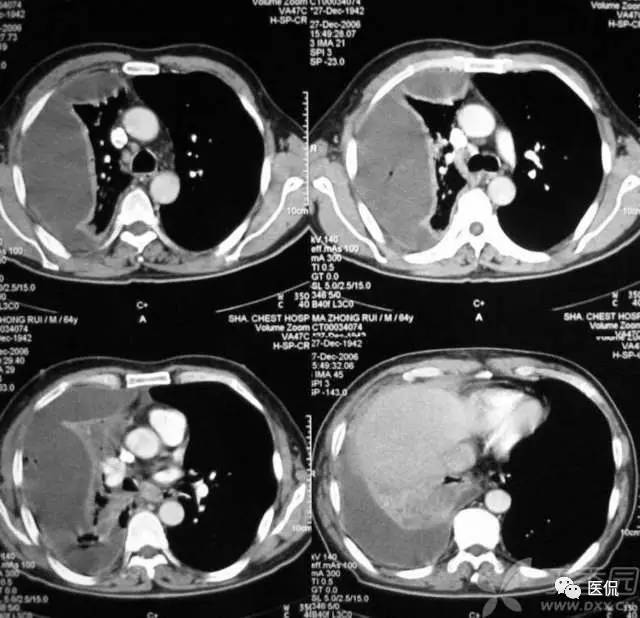

血管集束征

血管集束征在影像上表现为肺结节周围一支或几支血管到达瘤体内或在瘤体边缘截断或穿过瘤体的现象。其形成包括以下三种情况:

(1)肺血管进入肿瘤内或穿过肿瘤;

(2)肺血管受牵拉向病灶移位;

(3)肺血管到达肿瘤的边缘截断。

血管集束征的形成是由于肿瘤组织向血管支气管鞘或小叶间隔生长,瘤体内纤维组织增生或瘢痕形成,牵拉临近血管向瘤体集中所致。其中进肺门侧的血管束、支气管构成,血管壁多为扩张的小动脉,说明肺癌供血丰富;远肺门侧的血管束由扩张的小静脉组成,可能和静脉回流受阻有关。血管集束征的形成机制是由于恶性肿瘤细胞产生肿瘤生成因子诱发肿瘤形成新生血管,尤其是血供丰富的恶性肿瘤,由于其生长活跃,常致使肿瘤供血的血管代偿性增粗,这些血管长扩张或伴有肿瘤细胞的支气管动脉鞘浸润或瘤栓形成。这就意味着,肿瘤或结节周围血管是否增粗表明该病变的良恶性程度。血管集束征的出现与肿瘤或结节的大小有关,小于1公分的病灶较少出现;腺癌出现的的几率较高,因为腺癌供血丰富,纤维化形成的更明显。尤其要注意的是,一支血管引向结节或肿瘤内,不只仅见于恶性结节,也可见于良性病变如结核球、炎性假瘤或错构瘤。对于引向两性结节的这支血管可看作血管连接,而不是血管集束征。多支血管引向病变即出现了血管集束征这在恶性肿瘤出现的机会较高。此外,肺恶性结节累计静脉的机会更多,病灶不论大小,如果见到结节累及静脉,强烈提示恶性可能。判断某支血管是动脉还是静脉,主要根据其走形来判断,动脉主要和支气管伴行,静脉主要位于病灶的边缘绕行。关于血管集束征的血管,有学者认为大多数并非肿瘤供血血管或肿瘤血管,被肺癌卷入的肺动脉不参与肿瘤供血。另外,肺癌瘢痕的形成和癌巢的增殖与破坏与血管集束征和胸膜凹陷征的形成有关。血管集束征主要见于肺癌,尤其是腺癌和肺泡细胞癌。但是该征像不仅见于恶性肺结节,肺良性病变如结核球、球形肺炎等也可见到。所以仅根据血管集束征判断病变的良恶性并不是完全可靠的。

腺癌粗大的引流血管: